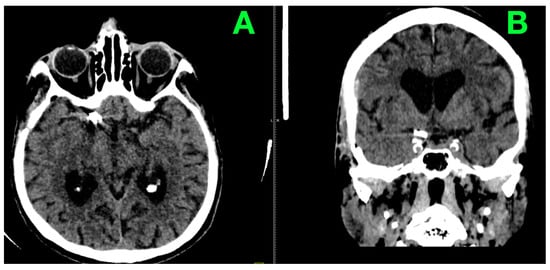

2. Case Presentation